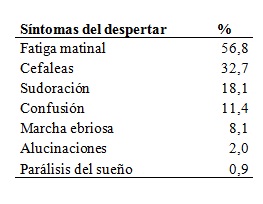

Se presentan los datos recogidos en la historia clínica electrónica desde 2008 a 2014 (n = 447, 291 mujeres y 156 varones). Por claridad expositiva, los síntomas se presentan agrupados en: síntomas durante el sueño, síntomas del despertar y síntomas de la vigilia en la Tabla 2, Tabla 3, y Tabla 4.

Tabla 3: Síntomas del despertar

Tabla 3. Frecuencia de pacientes con síntomas relatados en el despertar (n=447).

El ronquido y la somnolencia diurna excesiva persistente fueron los síntomas más frecuentes. La escala de somnolencia de Epworth tuvo un puntaje promedio de 10,4 ± 6,2. Utilizando el límite de corte habitual de 10 puntos, la sensibilidad para predecir más de 5 apneas por hora de sueño fue de 84,3% y la especificidad 16,4%. El 48,6% de los pacientes tuvieron un puntaje igual o mayor a 10, que indica somnolencia moderada a severa. No se encontró correlación entre el puntaje y los índices de severidad de las apneas del sueño: índice de apneas-hipopneas por hora (IAH), Índice de desaturación de oxígeno (IDO) e Índice de despertares (Idesp).

El conocimiento de la presentación clínica del SAHOS ha sido uno de los objetivos principales de nuestro estudio. El abordaje más completo probablemente sea el que utiliza el método estadístico de análisis de conglomerados25. En esa línea de investigación se inscribe la búsqueda de fenotipos fisiopatológicos o conductuales26, que puedan explicar las causas no anatómicas del SAHOS. La descripción de la clínica y de los hallazgos fisiológicos de nuestros pacientes referidos desde 1991 a 1998, fue presentada previamente27. Esta primera revisión de la presentación clínica, probablemente con errores de muestreo, sobresaliencia y ponderación, nos permitió sentar las bases para la recolección prospectiva, con una historia clínica electrónica, de síntomas, signos, repercusiones funcionales, factores de riesgo y factores agravantes. El formulario creado para el ingreso de los datos constituyó, además, un recurso didáctico adicional. Los síntomas principales fueron el ronquido y la somnolencia. Para evaluar a la somnolencia y catalogarla como diurna, excesiva y persistente (característica singulares del SAHOS) se requirió un entrenamiento específico. ya que muchas veces el síntoma es negado, ocultado por vergüenza o simplemente admitido como una característica peculiar innata. La escala de Epworth mostró valores similares a otras series publicadas y resulta inespecífica para su evaluación. EL FOSQ nos ha resultado un instrumento adecuado en el ámbito de la investigación clínica, pero no resulta práctico en la asistencia. Entre los síntomas peculiares, la frecuencia de la nocturia y del reflujo gastroesofágico son destacables, ya que habitualmente se atribuyen a otras patologías28)(29.